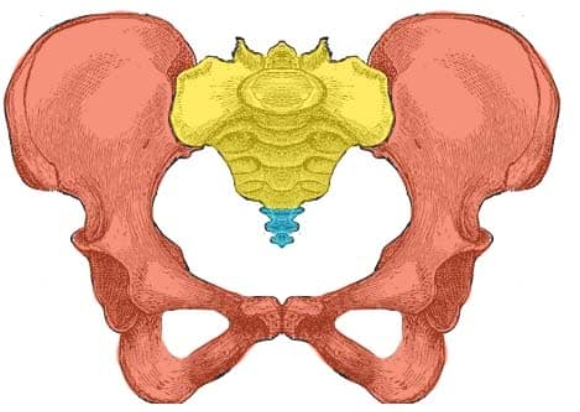

What is this region as a whole?

Pelvic Girdle